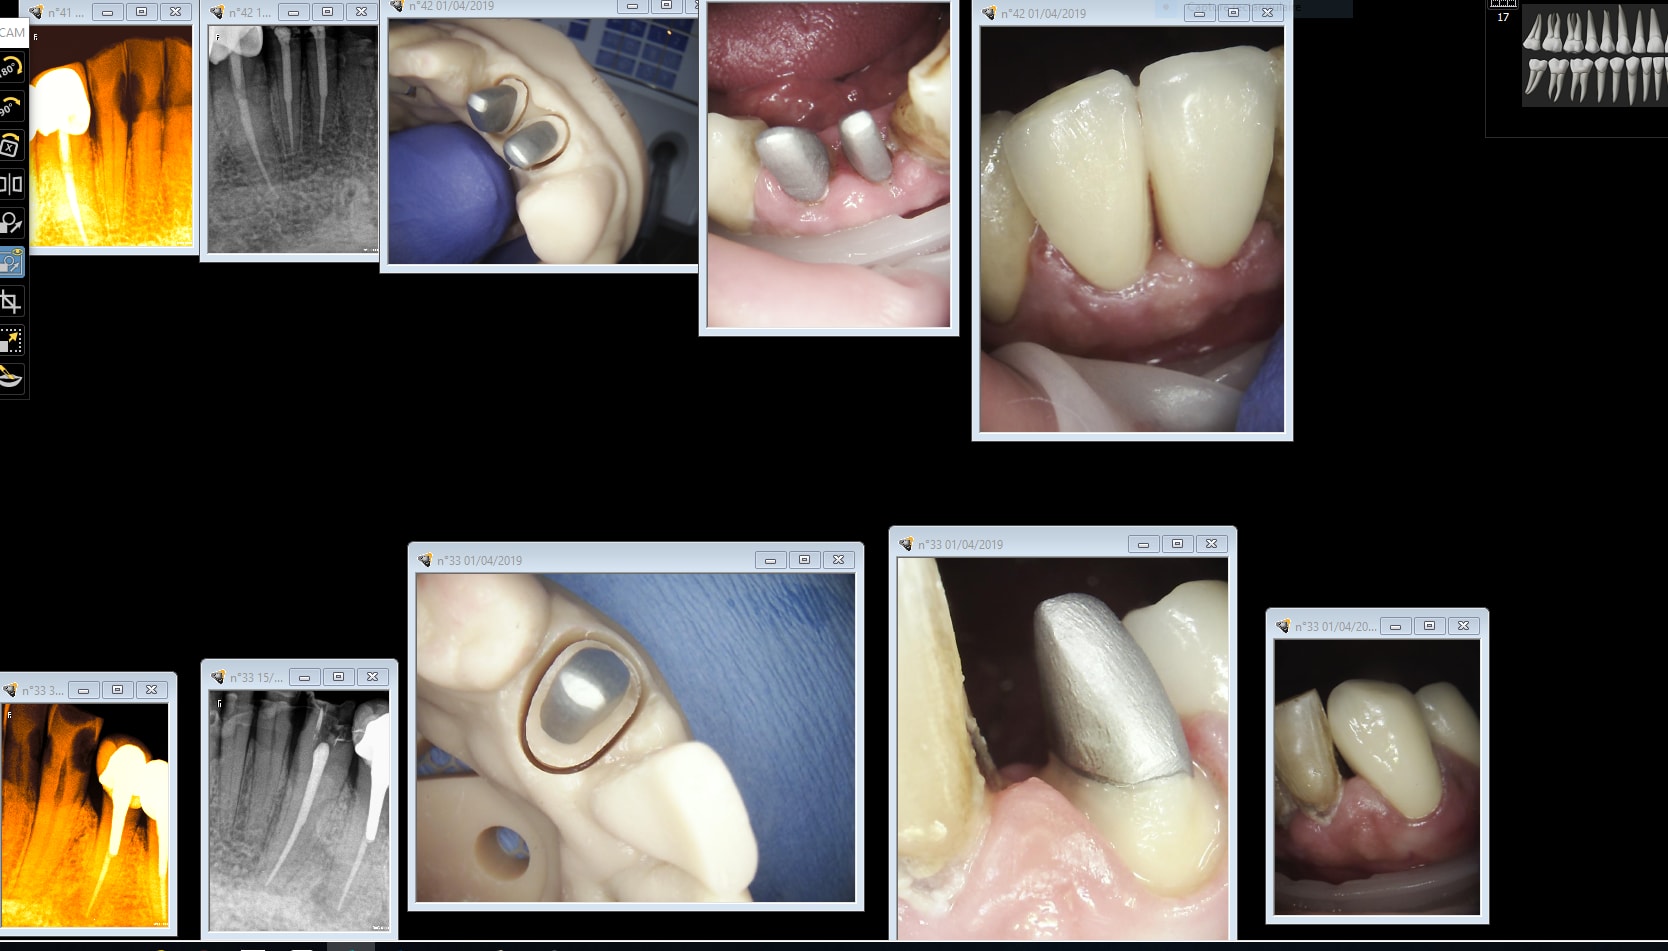

pl trt = ccm /12 avec inlay core, donc tarif plafonné.

1er rdv = prepa IC + provisoire à tenon

2ème rdv = pose IC avec 2ème provisoire (je ne fais pas ic + ccm en une fois)

> 1er rdv = prepa IC + provisoire à tenon

> 2ème rdv = pose IC avec 2ème provisoire (je ne fais pas ic + ccm en une fois)

Lors de ma prepa IC, je ne fais pas de taille périphérique, ou à minima lorsqu'il y a une provisoire à tenon, mais jamais en sous gingival, donc aucun saignement et aucun problème pour l'empreinte.

Pour l'instant, j'utilise encore l'empreinte "chimique" pour les prepa IC, car pas trouvé les scanpost pour les tenons Concours, mais l'empreinte de couronne, je la fait avec la Medit (tu sais, celle qui coûte moins cher qu'une Trios monochrome, mais avec la couleur en plus -)))

Autre possibilité (esthétique), tirer t’es provisoires d’un wax-up et facturer ton wax (éventuellement ton mock-up) d’une part (au tarif qui te convient) et ton provisoire d’une autre part....problème réglé. Maintenant pour des cas simple sans visé esthétique et avec une fonction facilement prévisible, le one shot est parfaitement efficace, et cela n’a aucun rapport avec une Richmond sauf si la taille périphérique permettant l’effet de férule et le forage du tenon ont des axes identiques (rares). Je me permets de critiquer le fait de réaliser un IC sans avoir au préalable préparé les limites de la taille car il est alors difficile d’appréhender les épaisseurs de dentine résiduelle entre l’IC et la taille périphérique. Enfin les tenon concours ont des profils similaires aux Apol dont tu trouveras les scan posts chez 3shape

Pour la technique de prépa sans taille périphérique, je ne l'ai pas inventée mais apprise dans le service du Pr Al...y (je ne pense pas qu'il soit très correct de citer des gens que l'on estime sans leur accord). Le principe, c'est de laisser au prothésiste le choix de l'axe et de la dimension de l'IC idéal pour la future couronne (il est bien mieux placé que nous, dans tous les sens du terme, pour ce travail) . après la pose de l'IC, l n'y a plus qu'à suivre l'IC pour la taille (un gosse de 5 ans pourrait le faire).